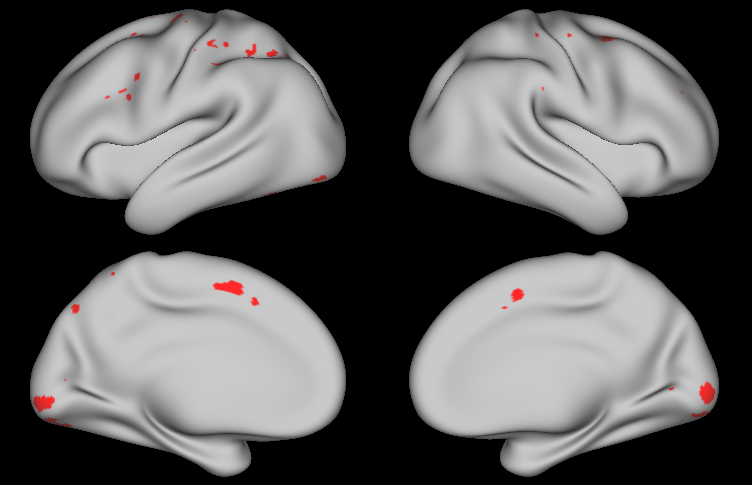

Figure LABEL:fig:sim99 displays estimated regions of activation obtained by thresholding the joint PPMs, marginal PPMs, and corrected p𝑝p-values using a significance level of 0.010.010.01 (see Figure S2 in Appendix B for regions of activation based on significance level 0.050.050.05). The false positive rate (FPR) and false negative rate (FNR) are reported for each method and activation, relative to the true active regions shown in Figure LABEL:fig:act. The Bayesian joint PPM method significantly outperforms the classical GLM using either FDR or FWER correction, simultaneously achieving lower FPR and FNR for both activations. This illustrates that the classical GLM approach not only results in a higher rate of false positives, but also suffers from reduced power. Finally, as expected, the marginal PPM approach yields more false positives than the joint PPM approach because it fails to appropriately correct for multiple comparisons.

Joint PPM Marginal PPM FDR FWER

Activation 1

[Uncaptioned image] [Uncaptioned image] [Uncaptioned image] [Uncaptioned image]

FPR 0.56% FPR 1.11% FPR 1.51% FPR 1.35%

FNR 0.08% FNR 0.00% FNR 1.59% FNR 1.91%

Activation 2

FPR 0.16% FPR 0.64% FPR 0.48% FPR 0.24%

FNR 0.88% FNR 0.48% FNR 3.58% FNR 3.74%